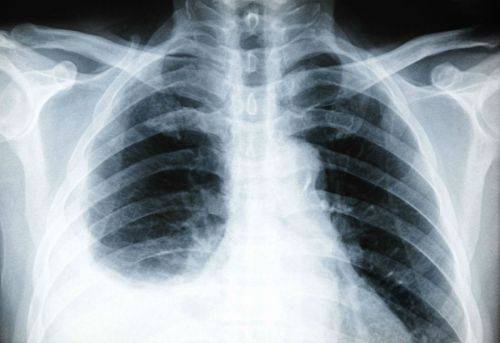

Плеврит — скопление воспаленной жидкости в правой плевральной полости, является осложнением пневмонии, признаком туберкулеза легких. Раздражение плевральных листков вызывает сильную боль сзади в области нижних ребер и в подреберье с иррадиацией в живот, невозможность глубокого дыхания, одышку, отставание правой стороны грудной клетки в акте дыхания.

На рентгеновском снимке видна жидкость в плевральной полости справа, чтобы точно узнать причину плеврита необходимо сделать повторный снимок после ее удаления

У пациентов общее тяжелое состояние, выраженная интоксикация, ознобы, высокие скачки температуры. Плеврит может быть вызван абсцессом легкого, раковой опухолью, нагноившимися бронхоэктазами.